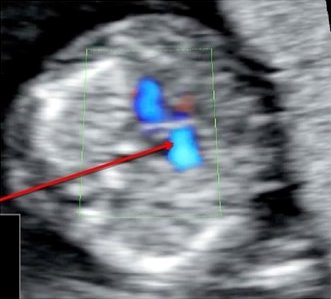

Оцените данные изображения и клип сердца плода в 13 недель и поставьте диагноз

Обсуждение вопроса 4

- У плода есть дисплазия трикуспидального клапана, приводящая к выраженной трикуспидальной регургитации и увеличению правого предсердия

- Трикуспидальный капан не смещен, регургитация начинается от клапана, а не от верхушки сердца, что позволяет исключить аномалию Эбштейна